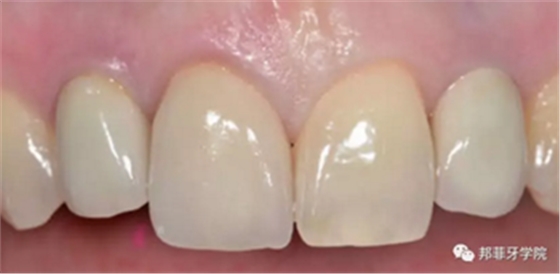

26歲女性患者,雙側(cè)上頜側(cè)切牙先天缺失,對(duì)原有修復(fù)體的“形態(tài)”、“光澤”等方面不滿意,希望重新修復(fù)(圖1&2)。12及22原為粘接橋修復(fù),11根管治療史;拆除原修復(fù)體后余鄰牙完整,未見病理性探診深度。無系統(tǒng)疾病史。患者期望值較高,告知治療流程佩戴臨時(shí)卡環(huán)義齒等(圖3)、費(fèi)用、風(fēng)險(xiǎn)后表示接受治療。

圖1:治療前口內(nèi)情況

圖 15-1:六個(gè)月后復(fù)查

圖 15-2:六個(gè)月后復(fù)查

圖 16-1: 六年后復(fù)查

圖 16-2: 六年后復(fù)查